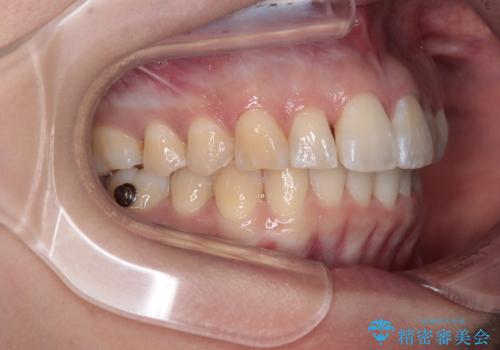

- インビザライン

- 1年8ヶ月

- 5-10回